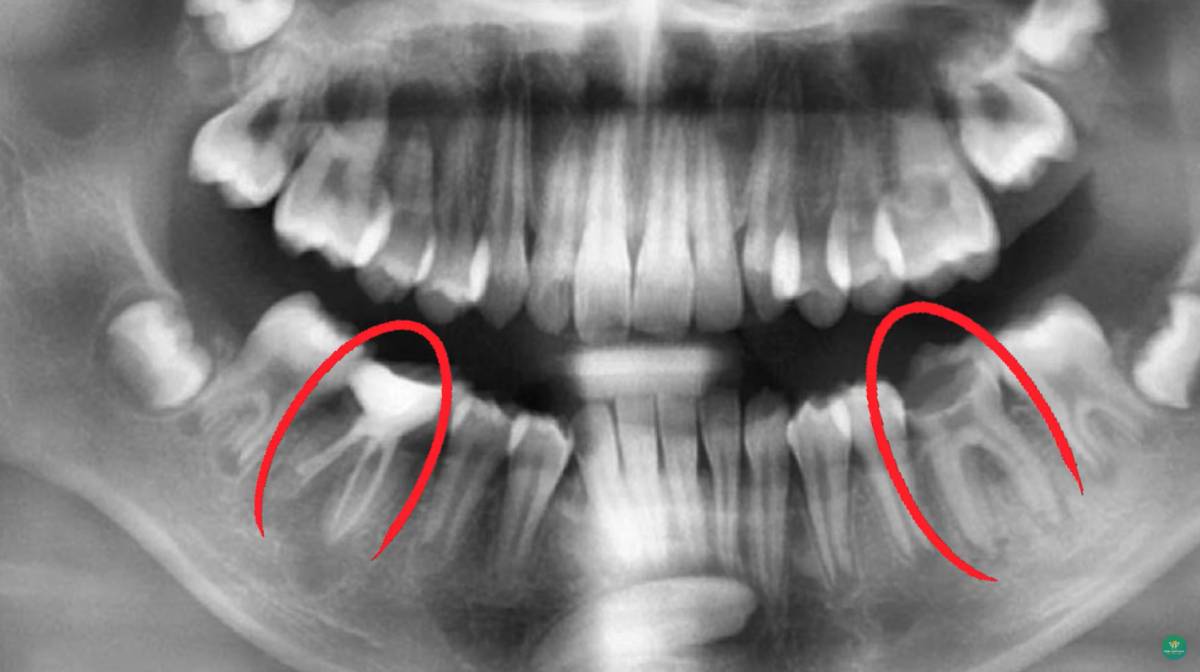

Răng mọc ngầm là tình trạng răng không thể mọc trồi lên khỏi nướu hoặc mọc lệch, mọc ngang, nằm sâu trong xương hàm. Tình trạng này thường xảy ra ở răng khôn (răng số 8), nhưng cũng có thể xuất hiện ở răng nanh hoặc răng hàm nhỏ.

Khi răng không có đủ chỗ để mọc hoặc mọc sai hướng, nó sẽ bị “kẹt” lại trong nướu và xương, gây ra nhiều biến chứng nguy hiểm.

Để xác định chính xác tình trạng răng mọc ngầm, bác sĩ sẽ chỉ định chụp X-quang toàn hàm hoặc CT Cone Beam. Nhờ đó, có thể đánh giá được vị trí, chiều hướng mọc, mức độ ảnh hưởng đến răng và xương xung quanh.

Việc chẩn đoán sớm giúp lên kế hoạch điều trị kịp thời, giảm nguy cơ biến chứng và bảo vệ răng vĩnh viễn.